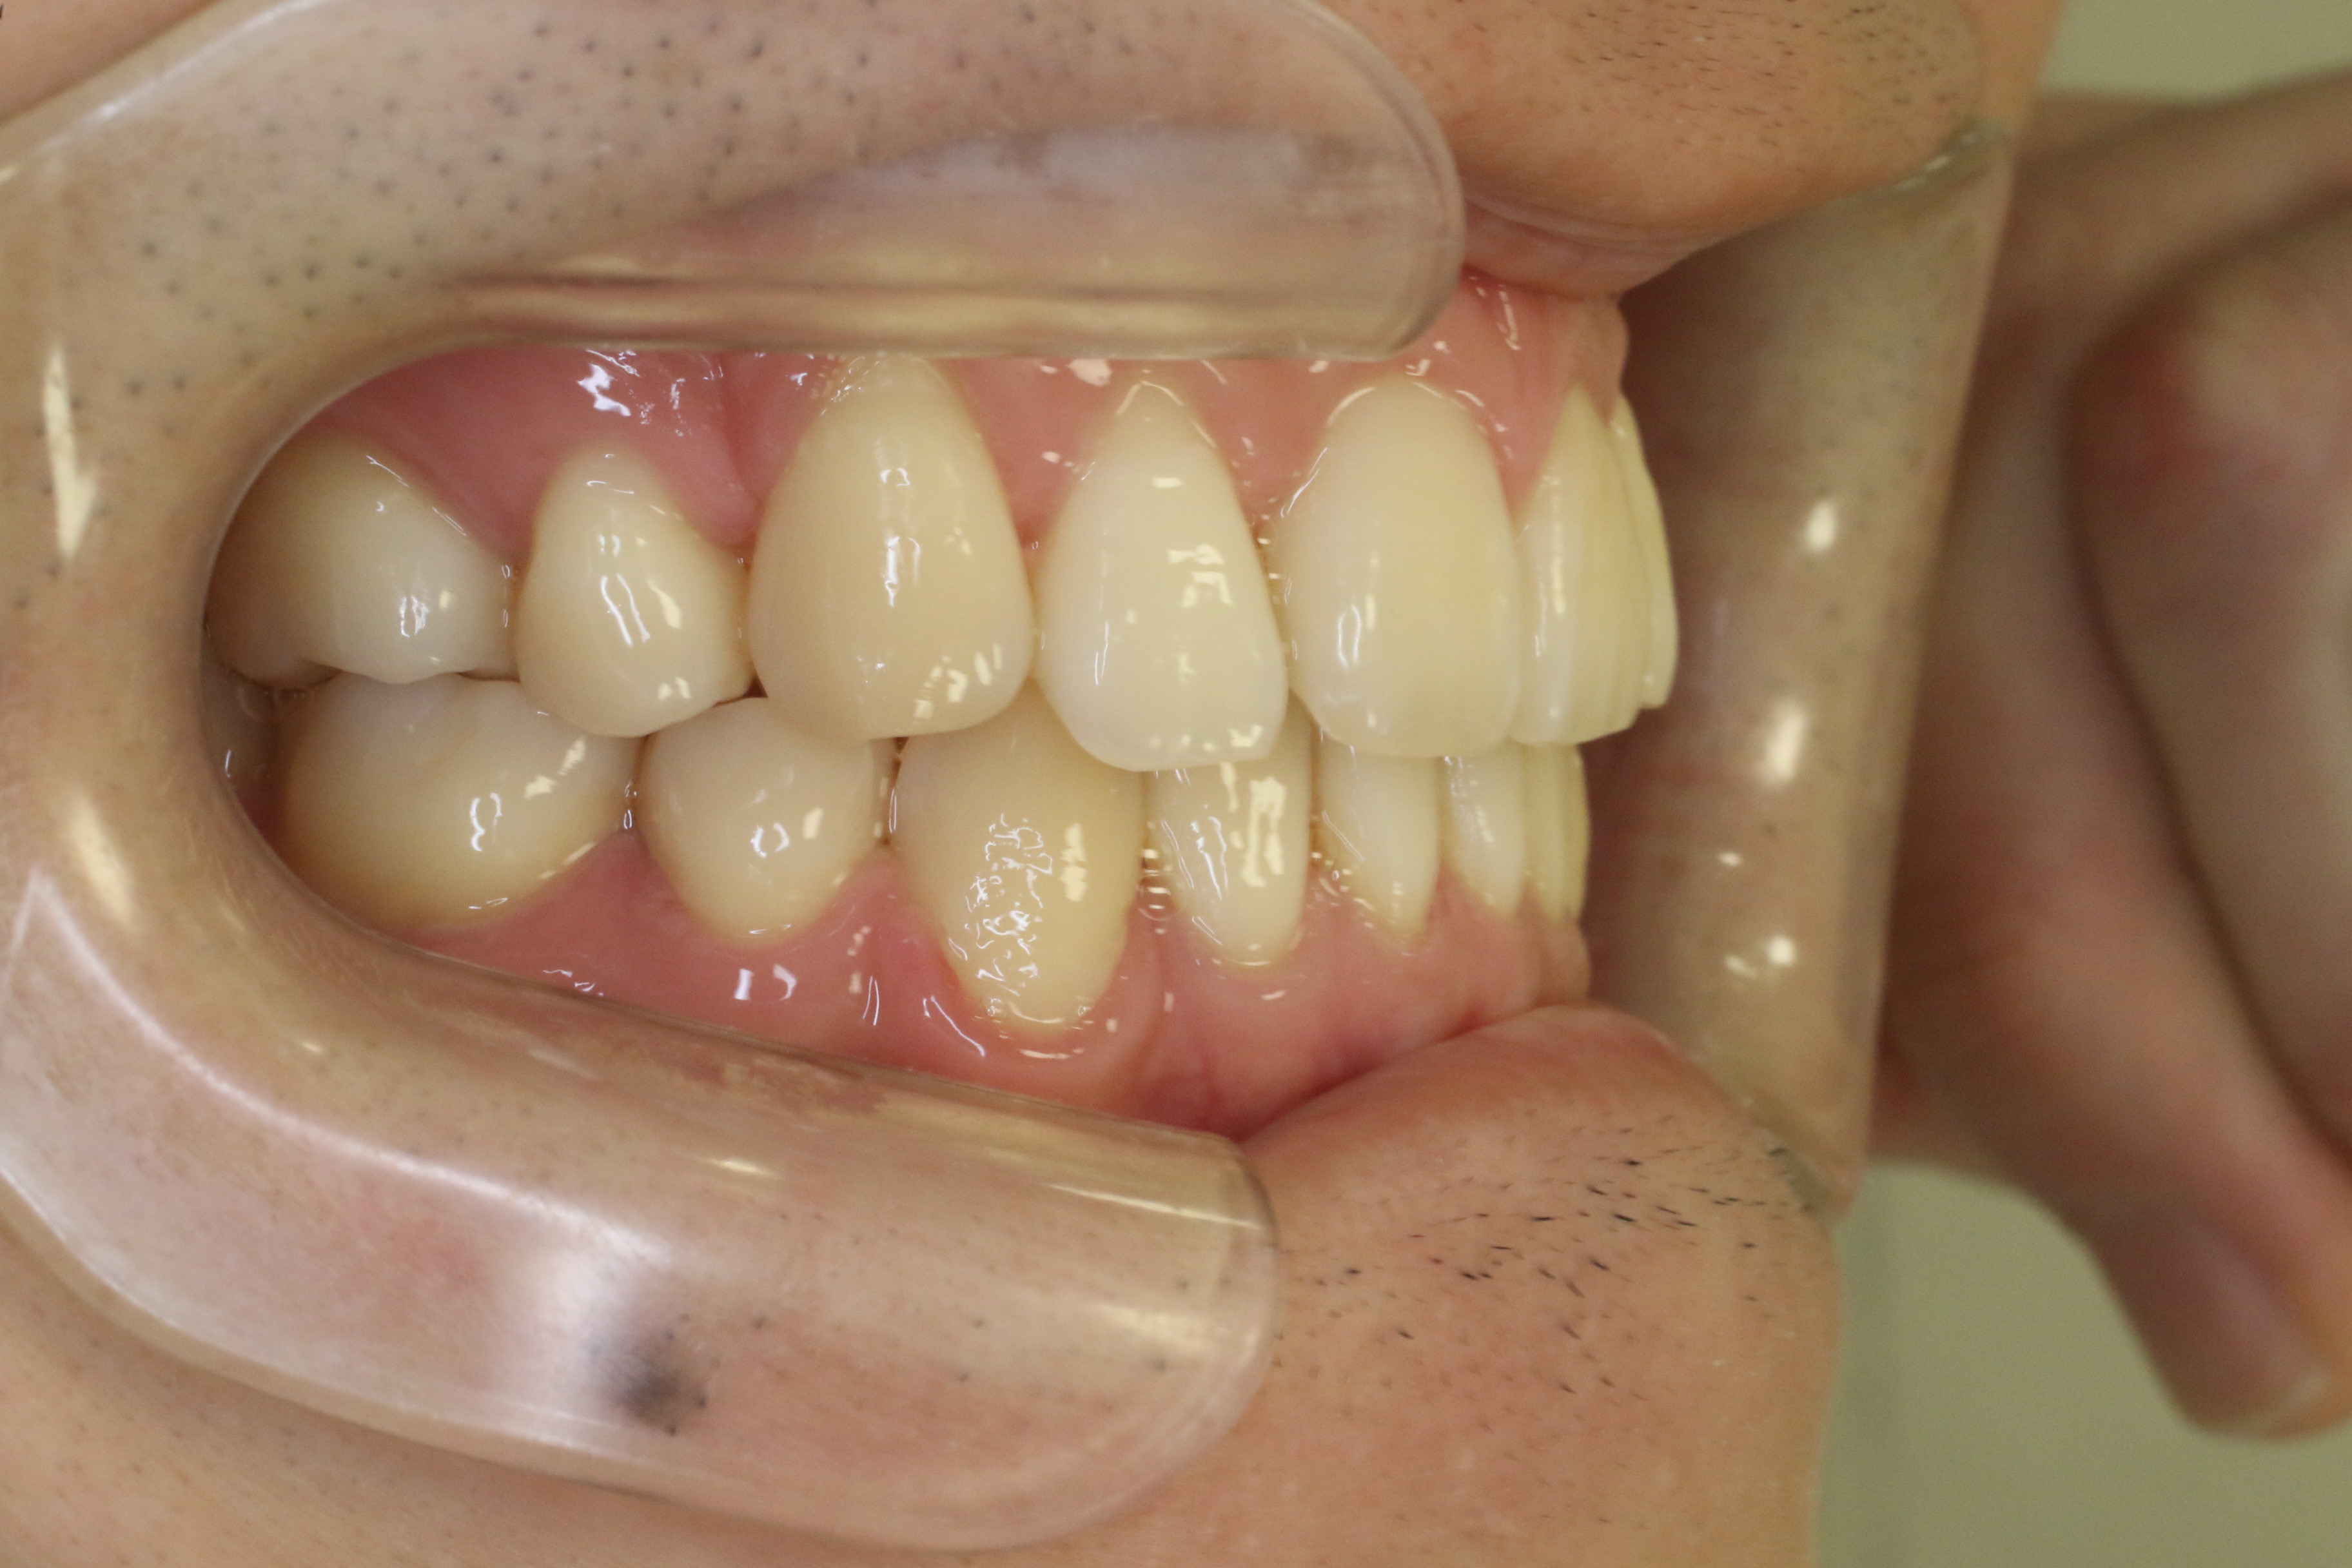

前歯の隙間が気になる

年齢層 30代

性別 女性

主訴 前歯の隙間が気になる

治療費用 1.287.000円

治療期間 9か月(来院回数10回)

抜歯 非抜歯

矯正の装置 ハーフリンガル

副作用、リスク ・知覚過敏・痛み・発音障害・体質により金属アレルギーの発症・歯肉退縮・歯根吸収・ブラックトライアングル(歯と歯の間の根元にできる隙間)・歯磨きが上手く出来ない場合、むし歯や歯周病が進行・保定が不十分の場合、後戻りの可能性

Before

After